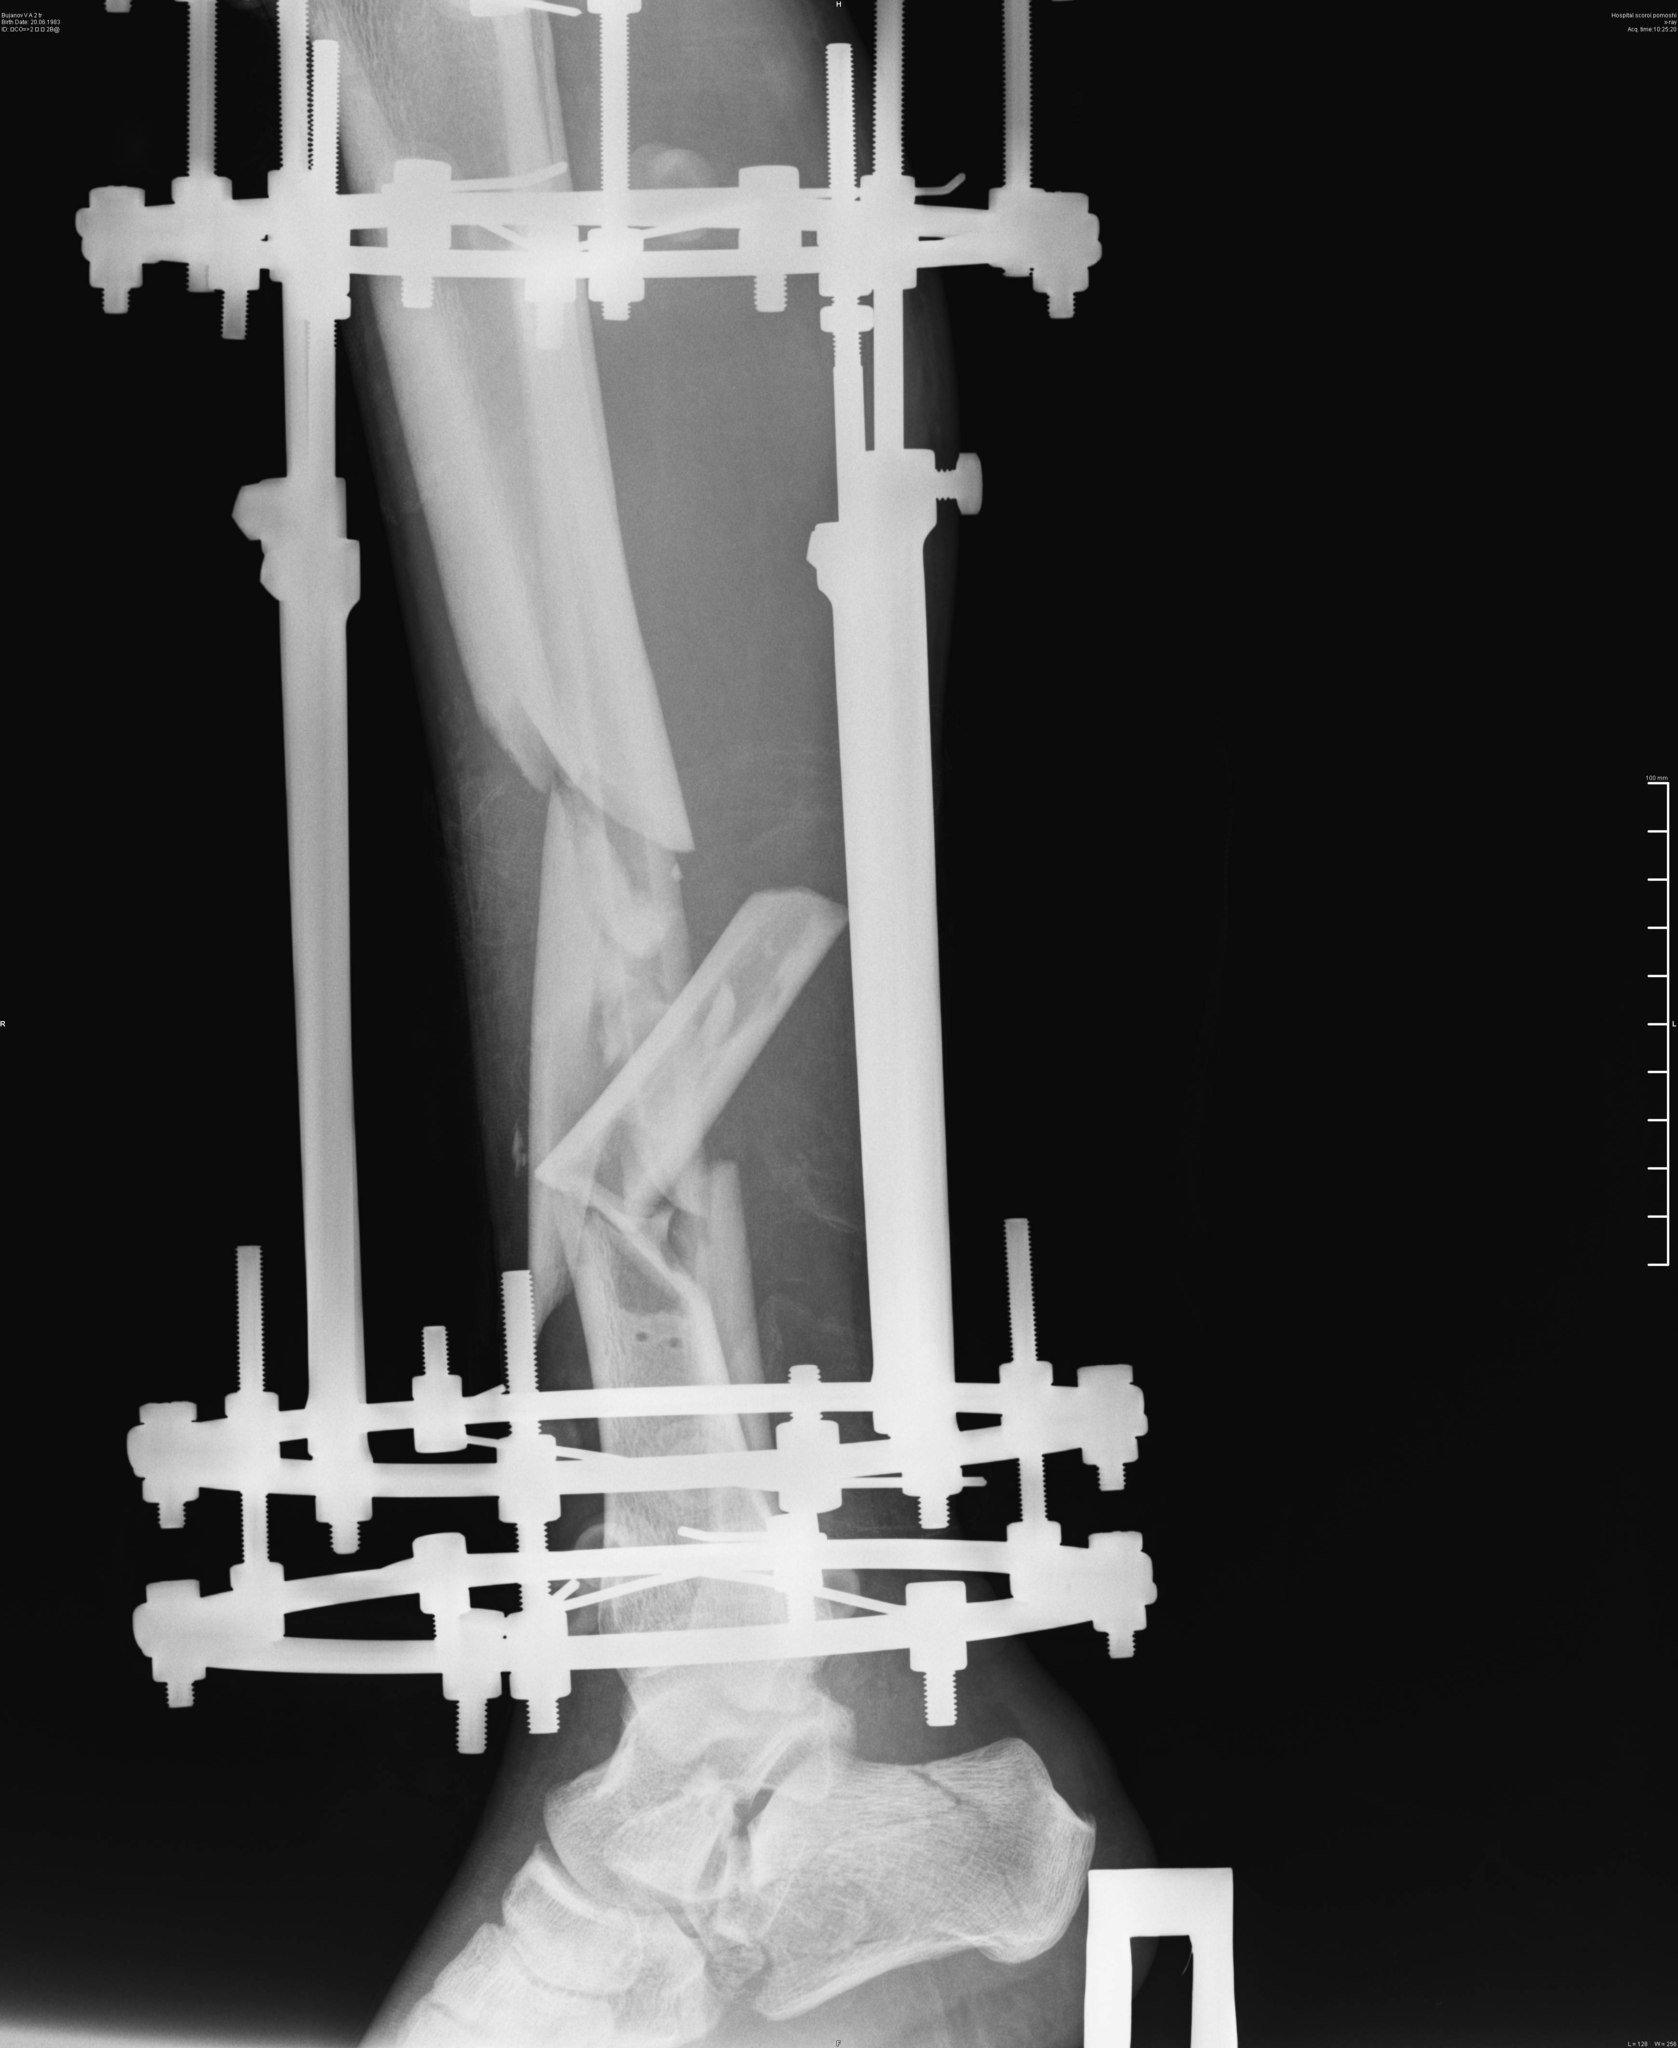

Эпикриз: Сочетанная травма. ЗЧМТ. Сотрясение головного мозга. Открытый многооскольчатый перелом обеих костей с/3 правой голени со смещением отломков. Открытый многооскольчатый перелом пяточной, ладьевидной, кубовидной кости, подвывих пяточной кости. Обширные рваные раны области правой стопы, правой голени.

было это еще 7 июня, но до сих пор, по прошествии двух операций ему не собрали все кости. Оказалосьь, что одну кость забыли на месте ДТП и теперь вместо нее требуется имплант. На одной ноге у него сейчас 18 переломов и 3 из них гниют, один из кусков кости встал поперёк, врачи опасаются её доставать или разворачивать, ибо можно занести ещё больше инфекции, если делать, то надо делать сразу всё комплексно, а пока приходится постоянно чистить, чтоб не было заражения, никакие обезболивающие уже не помогают, организм уже к ним адаптировался, и приходится терпеть эти боли. Нам же остается только медленно собирать деньги.

Сначала говорили про 250 т.р и 3 операции, но после поездки в Москву, в институт травматологии, сказали, что требуется не менее 500 т.р. только на 6 операций не учитывая восстановления сухожилий, кровообращения или как его там правильно + аппарат Элизарова на 3 года, а вообще предложили стопу ампутировать.